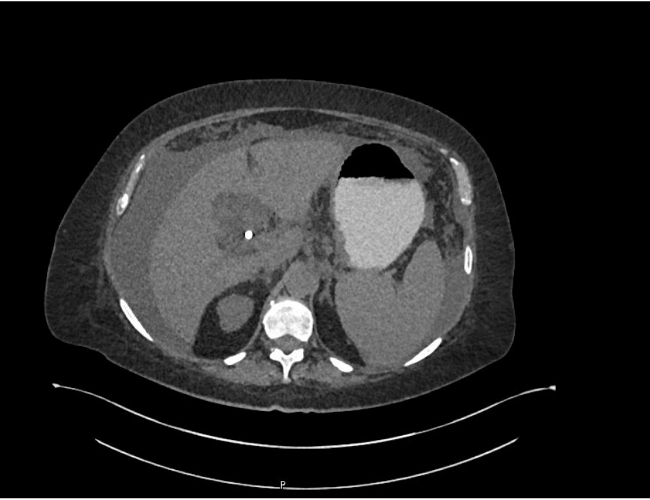

Xanthogranulomatous Pyelonephritis: An Uncommon Form of Pyelonephritis Highlighted in a Case Report

Danielle Malavazi Oliveira; Bárbara Sthefany de Paula Lacerda; Matheus Compart Hemerly, Maria Isabel Lima dos Santos, Weverton Machado Luchi